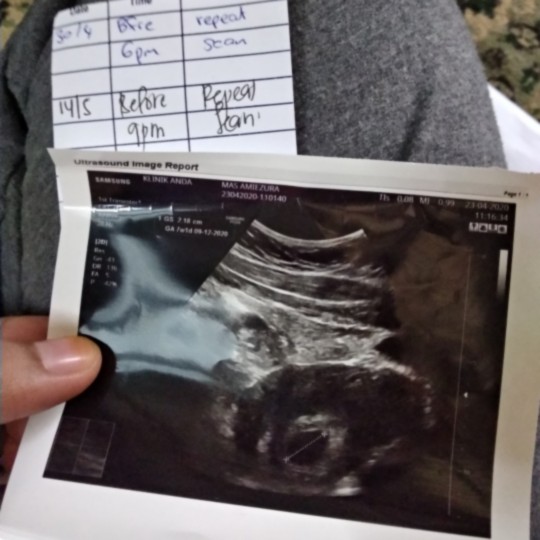

Nampak kantung je

Salam mommies ada pengalaman tak scan masa 6 weeks hanya nampak kantung je. Normal ke?